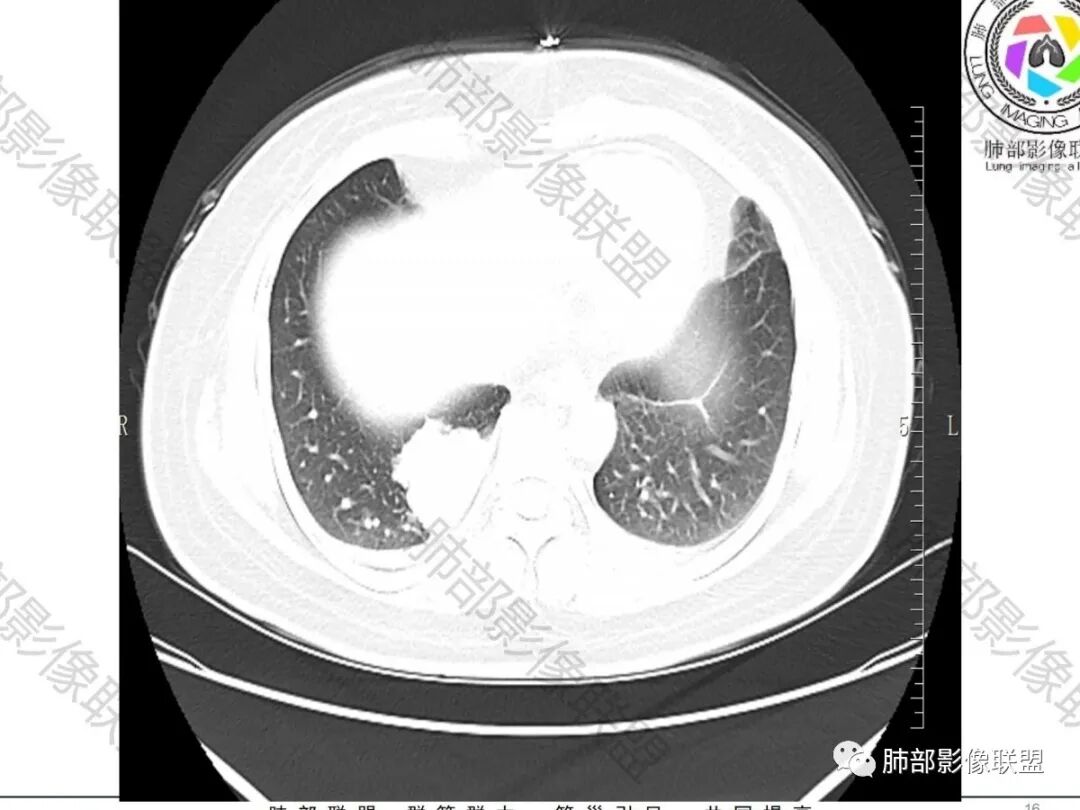

吴婧wj:    边缘平直,脂肪层清晰。与支气管关系并不密切。首先定位肺内应该没有问题。病变特点是囊性为主的,周围有一点是伴感染还是压缩肺?从这个密度来推测,可能的有:支气管囊肿,隔离肺血供不支持,结核,粘液腺癌,粘液腺瘤,肉瘤样癌。肉瘤样癌边缘不够膨隆。然后最后一个是转移。腹痛,到底有何联系,需要进一步腹部检查。

①部位及形态。多位于中下肺及内带,无感染时边缘清楚,呈圆形或卵圆形。②X线平片呈软组织密度,合并感染时内见气-液平面及邻近肺实变或边缘模糊的密度增高影。③CT检查可清楚显示其内部成分。无感染时,囊肿壁菲薄。囊内充满液体时为水样密度(0〜20HU),约50%病例因囊肿内蛋白成分、钙质及黏液而呈较高密度。10%见囊壁钙化。液体完全排出时为含气囊肿。本病常合并感染(75%),此时嚢肿迅速增大,囊壁增厚及强化,外壁变模糊,囊内出现气-液平面,形似肺脓肿,但治疗后病变可有明显变化。囊肿邻近肺组织由于压迫的活瓣样作用及侧支通气造成过度膨胀及空气潴留。④MRI T2WI 上均为高信号,T1WI 则因成分不同而为低信号、等信号或高信号,合并感染则为中等信号。

2.右肺下叶脊柱旁类椭圆形块影,边界清楚,密度偏低,隐约见轻度强化囊壁样结构,均匀一致,中央区域未见强化,因属囊样块影。前外缘处显示“壁外”小范围轻度强化软组织密度影,未见磨玻璃晕。

3.块影边缘见匍行血管影,未显示体循环供血。病灶与支气管关系未能显示或呈现。